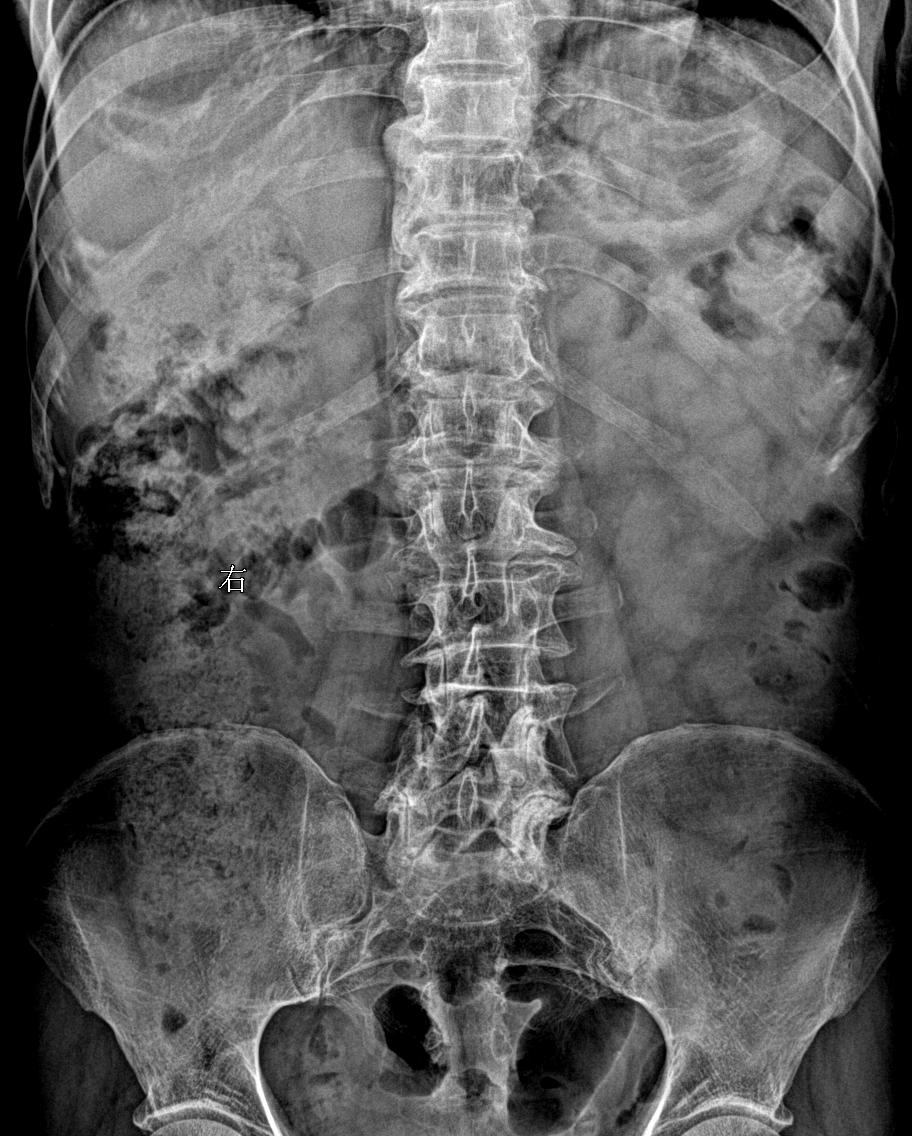

男,79y,腰疼就诊

2024-08-13 14:09

腰椎疼痛,下肢麻木酸疼

2024-06-03 19:19

腰椎疼痛,滑脱几度?

2024-06-03 19:32

腰部疼痛

2024-06-03 19:33